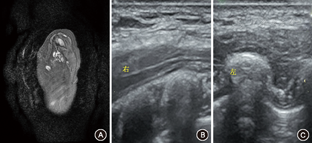

孕妇,26岁,孕1产0,2018年3月3日孕21周在温州医科大学附属台州医院常规产前检查,超声示单活胎,生长指标在正常范围,胎儿右侧腋下可见囊性团块大小21 mm×18 mm×16 mm,边界清,内可见一条分隔光带,液性部分透声可,血流信号不明显。超声诊断:胎儿右侧腋下囊性团块(淋巴管畸形),见图1A。其后每4周复查1次超声,团块进行性增大,孕37周+4超声显示胎儿右侧腋下胸壁外侧囊性团块大小为101 mm×110 mm×95 mm(图1B)。孕期超声随诊未发现胎儿伴发其他畸形。孕妇在外院行脐血细胞染色体核型分析,报告提示"脐血染色体320-400BPHS显带分辨率未见明显异常" (孕26周+3),进一步产前全基因组芯片扫描检测示"未检测到基因组内明显致病性拷贝数变异" (孕26周+6)。孕妇否认孕期用药史,孕妇夫妇否认任何遗传疾病,否认肿瘤、淋巴系统等疾病。

经超声科、优生优育科、产科、儿内科、儿外科会诊,因胎儿巨大团块位于右侧胸壁与上肢之间,且张力大致胎儿右上肢始终呈外展状态,胎儿有可能出现肩难产,决定在超声引导下行宫内胎儿囊性团块穿刺抽液术。孕38周+4胎儿右侧腋下胸壁囊性团块大小为101 mm×110 mm×95 mm,在超声引导下穿刺针刺入该团块腔内(图1C),抽出淡黄色清亮液体400 ml,实验室检查证实为淋巴液(淋巴细胞比例大于85%),见表1;术后团块缩小为62 mm×51 mm×21 mm(图1D)。再将博来霉素1 mg(瀚晖制药有限公司,1.5万单位博来霉素溶解于生理盐水5 ml)在超声引导下注入囊性团块内,每个分隔内都注入博来霉素进行硬化治疗。抽吸术后第2天,孕妇经阴道分娩一女活婴,1和5 min Apgar评分均为10分,右侧腋下胸壁情况见图2A;超声检查显示婴儿囊性团块大小57 mm×47 mm×38 mm(因当时为床边B超,未存图片)。生后42 d复诊,在超声引导下将博来霉素2.5 mg(用生理盐水5 ml溶解)注入囊性团块内。随访10个月时,婴儿状况良好(图2B),MRI检查未见明显囊性团块(图3A)。随访30个月时,超声复查仅皮下软组织增厚,内无液性暗区(图3B),左侧腋下胸壁软组织正常(图3C)。